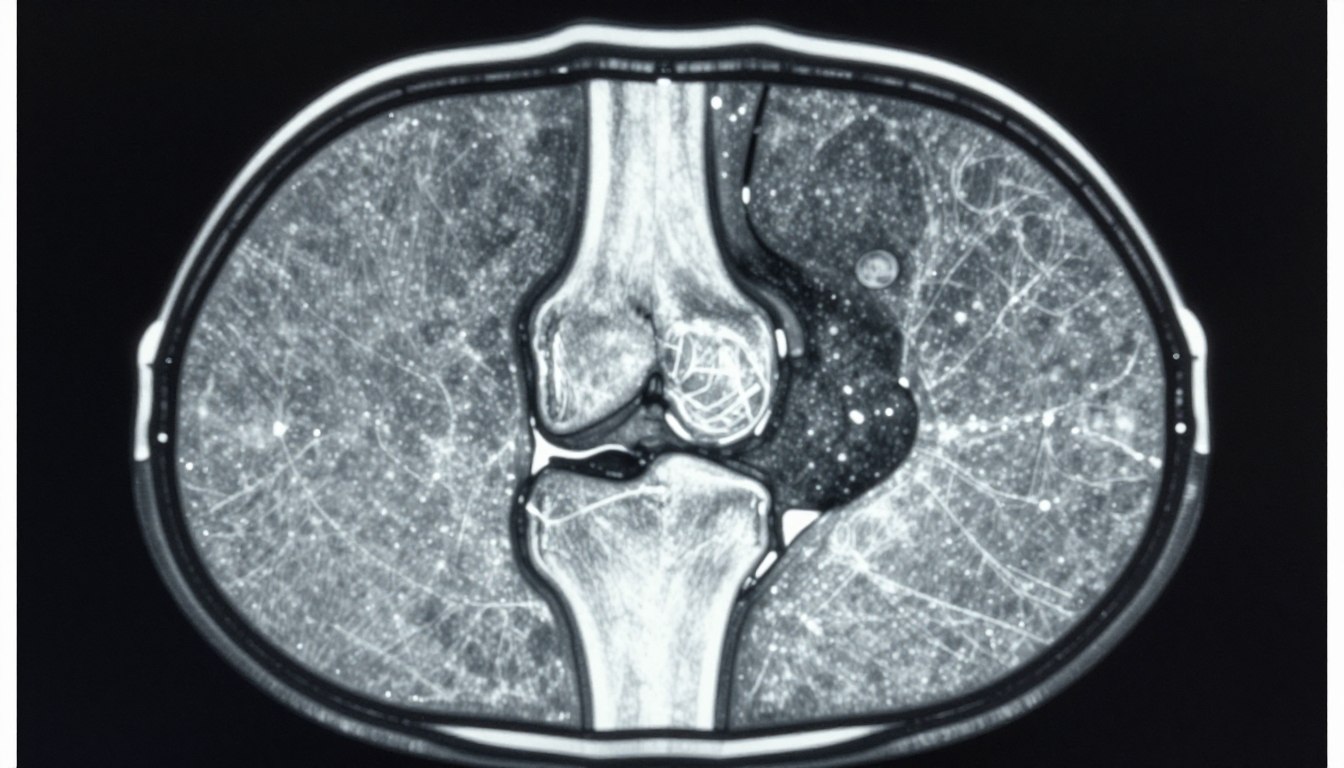

Imaging and Structural Outcomes

Exploratory imaging assessments evaluated potential structural benefits of LEVI-04 treatment. While the study period was relatively short for detecting cartilage changes, preliminary data suggest possible disease-modifying effects.

MRI measurements of cartilage thickness and composition showed trends toward preservation in the treatment group compared to placebo. Longer-term trials will definitively establish whether LEVI-04 can slow structural progression.